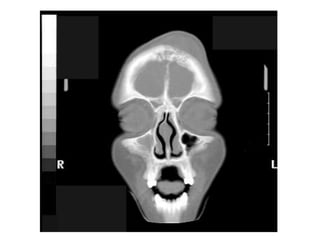

This document discusses sinus imaging using CT scans. It first describes the different sinus cavities in the anatomy: frontal, maxillary, nasal, ethmoid and sphenoid. Second, it lists common sinus pathologies seen on CT such as sinusitis, fungal sinusitis, deviated septum, sinus polyps, mucoceles, concha bullosa and sinus cancer. Finally, it presents two case studies and asks questions to test understanding of sinus conditions and anatomy.